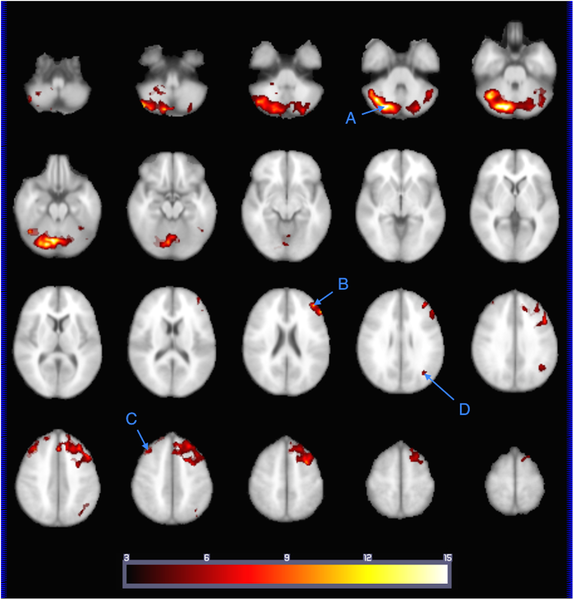

Now, regarding the second set of images, they depict results obtained using a different technique called Tract-Based Spatial Statistics (TBSS) (Hutton et al., 2020). TBSS is still based on DTI data but utilizes a different analytical approach. Instead of directly analyzing FA and RD values across the brain like in the first set of images, Tract-Based Spatial Statistics (TBSS) typically involves aligning the DTI data from multiple individuals onto a common template or skeleton. This process allows researchers to compare and analyze white matter integrity across all subjects in a standardized way. So, while both sets of images involve DTI and analyze FA and RD, they utilize different analytical methods (standard analysis vs. TBSS) to examine how screen media use influences white matter integrity in preschool-aged children.

The lateral and medial views allow researchers to observe which tracts are particularly affected by screen media use and how these alterations are distributed throughout the brain (Hutton et al., 2020). The data from all 47 preschool-aged children are combined and analyzed together. The color-coded areas on the brain represent regions where differences in Fractional Anisotropy (FA) or Radial Diffusivity (RD) values are observed across the entire group in relation to their screen media use.

By analyzing the data from all 47 children together using TBSS, researchers can identify consistent patterns or trends in white matter alterations associated with screen media exposure across the entire study cohort (Hutton et al., 2020). This approach helps ensure that the observed trends are not just isolated occurrences in individual participants but are instead meaningful and representative of the group as a whole. It allows researchers to draw more robust conclusions about the relationship between screen media use and brain development in preschool-aged children.

TBSS helped identify areas of the brain where the structural integrity of white matter tracts differed depending on the amount of screen time children were exposed to (Hutton et al., 2020). These differences suggest that prolonged screen media use may influence the microstructure of certain brain regions involved in various cognitive functions.

TBSS and DTI both provided complementary information about the association between screen media use and alterations in white matter integrity. Both techniques revealed that higher ScreenQ scores, indicating increased screen media exposure, were correlated with changes in Fractional Anisotropy (FA) and Radial Diffusivity (RD) values in specific brain regions.

While DTI focused on analyzing the overall white matter integrity across the brain, TBSS specifically identified regions where these alterations were most pronounced. So, in a sense, TBSS reaffirmed the findings observed through DTI by pinpointing specific areas of the brain where the effects of screen media exposure were most notable.

This data collected from the study makes this image a gold mine (Hutton et al., 2020). We're able to observe the distinct effects on Fractional Anisotropy (FA) and Radial Diffusivity (RD) whilst also knowing the major functions that these different tracts serve. Given our knowledge of these major functions from previous brain studies, the observed increases and decreases in FA and RD become meaningful in terms of the specific functions being affected. The ability to interpret these increases and decreases in FA and RD—and to correlate them with the rise in screen time observed in our sample of 47 children—makes this image incredibly valuable.

We now understand that this study significantly focused on language and literacy development in relation to screen time, highlighting its impact on the cognitive, social, and emotional development of young children through cognitive processing. Additionally, attention span may be indirectly related to some cognitive functions mentioned, such as executive functions and speed of processing (Hutton et al., 2020). According to the table, the anterior thalamic radiation tract, which is associated with executive function, exhibited a FA decrease of 33% and 13%, and a RD increase of 18% and 10% in the left and right parts of the brain, respectively. Furthermore, the forceps minor tract, also related to executive function, showed an FA decrease of 55% and 56%, and an RD increase of 34% and 33% in the left and right sides, respectively. These changes suggest implications for altered attention spans among the sample of 47 preschool-aged children. Therefore, this study is not only an important source of evidence for immediate real-world application but also a topic worthy of further investigation in future research.